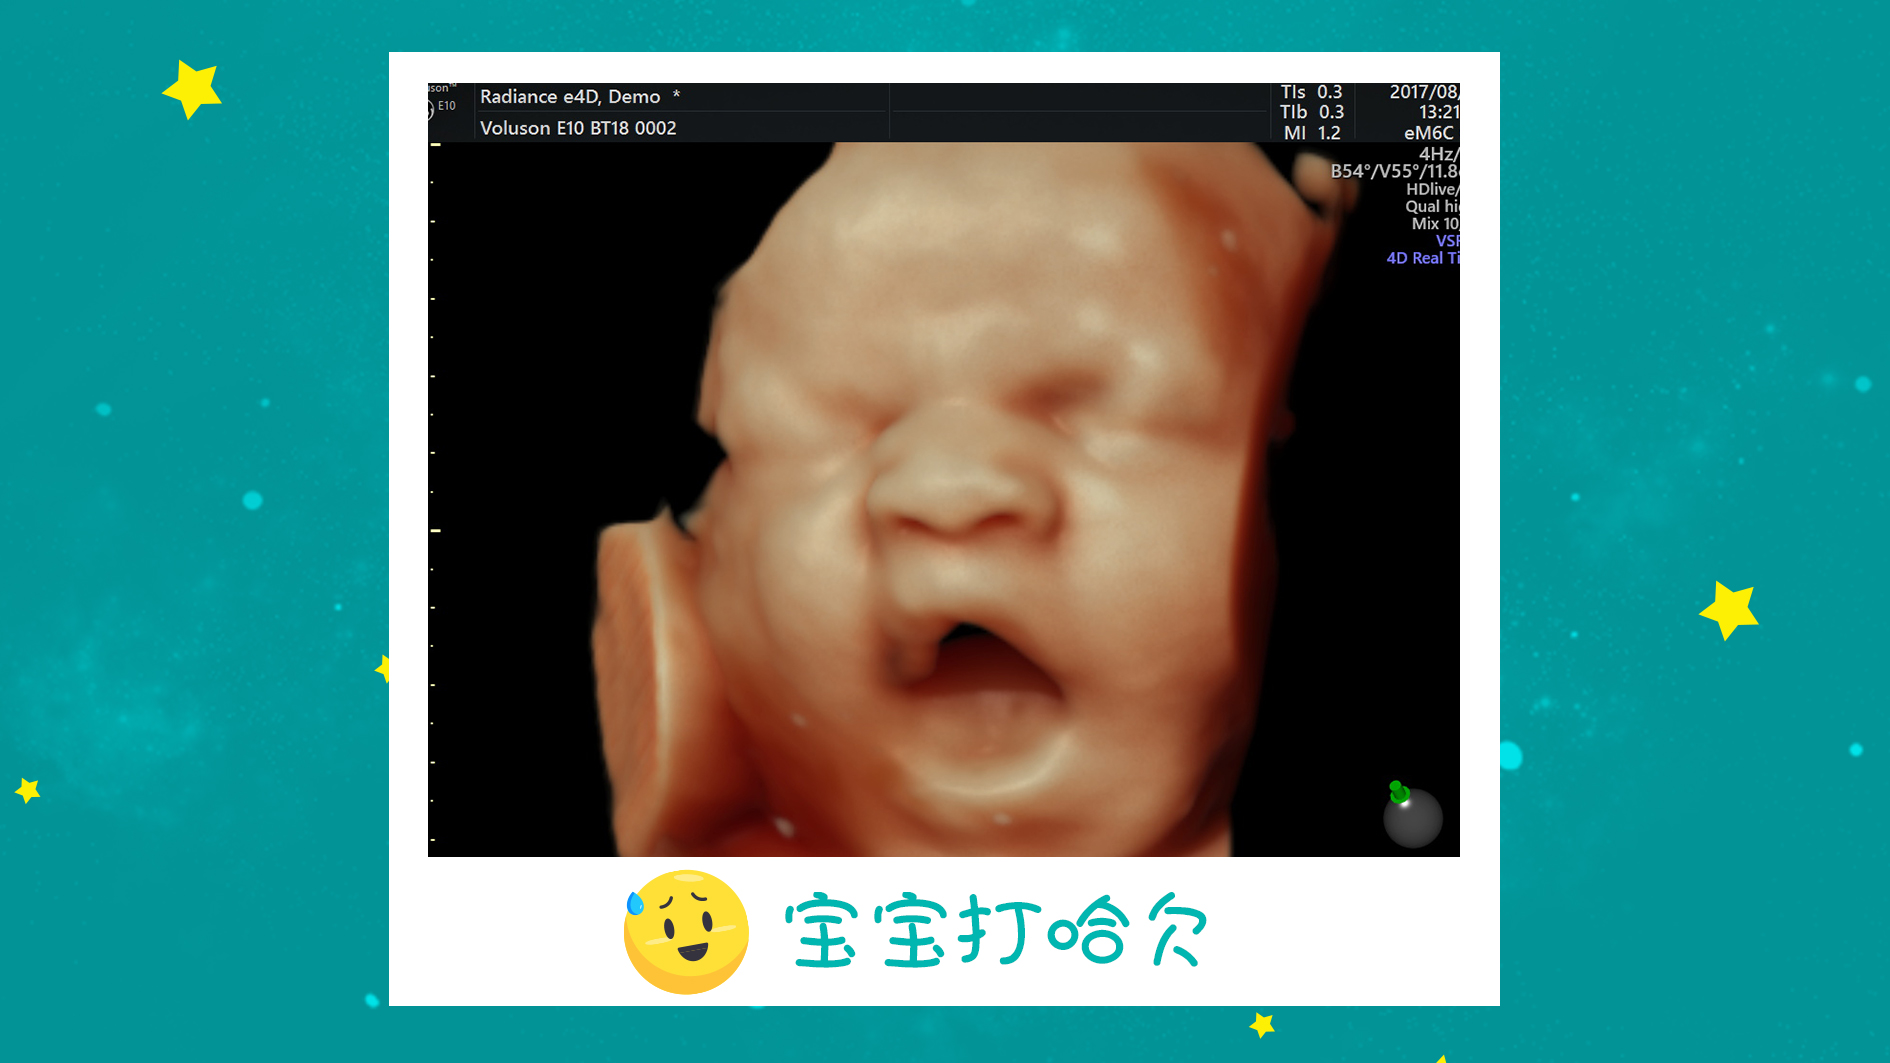

远东妇产医院使用的是美国GE-10高清四维彩超,也是目前ZUI高端的四维彩超设备,依托先进计算机技术,把一堆让人看不懂的数据变成了清晰的动态图像,宝宝健康与否一目了然,同时还能自动为胎儿进行宫内“写真”和动态录像,高清显示腹中宝宝的实时360°超真动态演示,画质堪比IMAX电影效果。

宝宝打哈欠、咀嚼、伸手等小动作一目了然,准妈妈还可以和宝宝超高清“隔空对视”哦。

在远东做四维彩超不仅安心,还能够让你与胎宝宝来次别样的会面,亲眼目睹胎宝宝在你的肚子里打哈欠、吸吮、揉眼睛等超多的卖萌瞬间,还免费赠送你胎宝宝四维照片,留住属于你和宝宝的珍贵回忆哦~